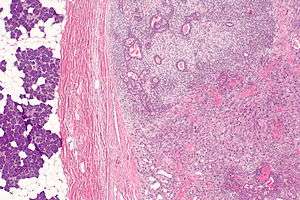

Micrograph of a carcinoma ex pleomorphic adenoma. The carcinoma component is on the lower right of the image. Benign parotid gland is seen at the left and pleomorphic adenoma is seen at the upper right. H&E stain.

Carcinoma ex pleomorphic adenoma, abbreviated ca ex PA, is a type of cancer typically found in the parotid gland. It arises from the benign tumour pleomorphic adenoma.